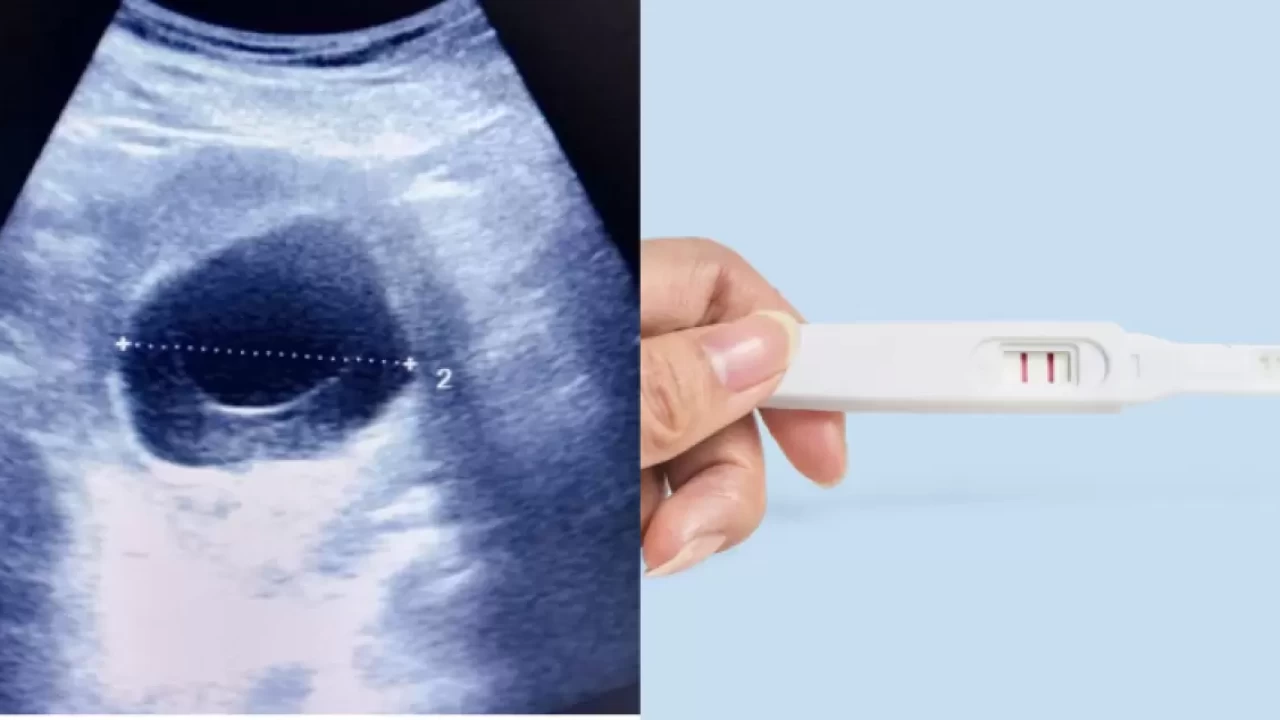

Tüp bebek süreci, başarılı bir gebelik için yumurtalık ve rahim hazırlığını gerektirir. Bu süreçte dikkat edilmesi gereken unsurlar arasında sağlıklı bir diyet, düzenli egzersiz, stres yönetimi ve tıbbi kontroller yer alır. Yumurtalık stimülasyonu ve rahim hazırlığı süreci hakkında detaylı bilgiler haberimizde!

Tüp bebek tedavisinde, yumurtalıkların uygun bir şekilde hazırlanması büyük önem taşır. Bu hazırlık, yumurtaların sağlıklı bir şekilde gelişmesi ve olgunlaşması için gereklidir. Aynı zamanda rahim iç duvarının kalınlaşması, embriyonun tutunması açısından kritik bir rol oynar. Kadınlar, bu süreçte doktorları tarafından önerilen hormon tedavilerini aksatmadan uygulamalıdır. Hormon seviyelerinin dengelenmesi, tedavi sürecinin başarısını doğrudan etkiler. Bu yüzden, düzenli doktor kontrolleri yapılmalı ve gerekli tıbbi tavsiyelere uyulmalıdır.